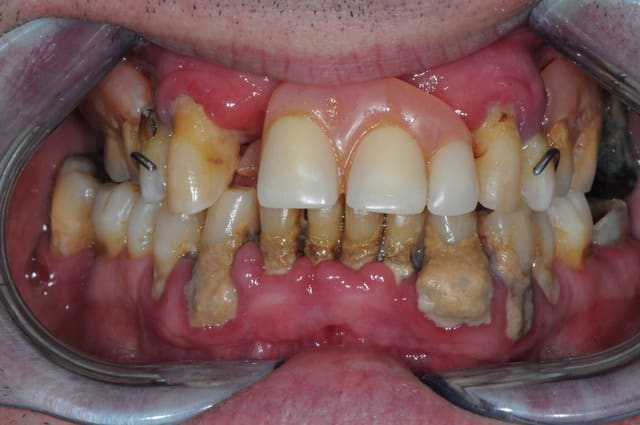

20 ans et toutes ses dents ! A la CMU de générations en générations....... status incomplet de 2003, et l'autre aujourd'hui 8 ans après. Et en 2003 avait poursuivi ses soins avec un lapin! ) On voit ce que donnent les dents dévitalisées et non couronnées dans le temps ) les autres aussi d'ailleurs ! ) C'est de la faute aux mauvais dentisss mon cousin !

Ceci dit c'est pas une star qui a couronné 31 et 41 )